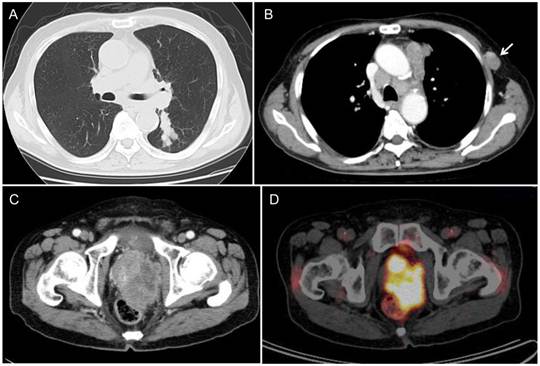

A 77-year-old man noted a swelling in the right neck and was referred to our department. Chest computed tomography (CT) revealed a tumor extending along the bronchus in the S6 region of the left lung, mediastinal lymphadenopathy, and a mass in the left chest wall (Figure 1A and 1B). The tumor marker NSE level (institutional cutoff value, 15.0 ng/mL) was elevated to 81.0 ng/mL, and ProGRP (institutional cutoff value, 46.0 pg/mL) to 346 pg/mL (Figure 2). LCNEC was diagnosed by bronchoscopic brushing cytology of the S6 tumor. Histologically, right cervical lymph node biopsy revealed solid nests of large tumor cells with finely granular chromatin and small nucleoli (Figure 3A and 3B). On immunostaining, the tumor cells were positive for cytokeratin AE1/3, thyroid transcription factor (TTF)-1 and N-CAM, leading to a diagnosis of metastasis of pulmonary LCNEC (Figure 3C, 3D and 3E). The patient received four courses of carboplatin and etoposide combination chemotherapy, achieving a complete response, with a normalization of NSE and ProGRP (Figure 2).

Figure 1

Radiological findings. (A, B) Chest CT revealed a peribronchial tumor in the S6 of the left lung and bulky mediastinal lymphadenopathy. The arrow indicates the lymphadenopathy in the left chest wall. (C) During post-chemotherapy follow-up, pelvic CT revealed a massive tumor in the prostate. (D) PET/CT demonstrated marked FDG uptake (SUVmax=19.0) in the prostatic tumor.

He developed symptoms of urinary retention four months after the completion of chemotherapy. Chest CT showed swollen mediastinal lymph nodes, and pelvic CT revealed a massive tumor in the prostate (Figure 1C).

The prostatic tumor was inhomogeneous, with irregular borders and compression of the urinary bladder and rectum. PET/CT showed FDG uptake in the mediastinal lymph node and in the prostatic tumor (Figure 1D). The tumor markers NSE and ProGRP were re-elevated to 54.5 ng/mL and 1,260 pg/mL, respectively (Figure 2), but the PSA was normal. Either prostatic metastasis of lung cancer or primary prostate cancer was suspected, and prostatic needle biopsy was performed. Histologically, the biopsy specimen showed tumor cell infiltration between normal prostate tissue and an absence of prostatic intraepithelial neoplasia in the adjacent glands (Figure 4A). The tumor grew in solid organoid nests consisting of polygonal tumor cells with abundant, finely granular chromatin and small nucleoli (Figure 4B). Immunostaining of the tumor cells was positive for cytokeratin AE1/3, TTF-1 and N-CAM (Figure 4C, 4D and 4E). These findings are similar to those of the neck lymph node biopsy specimen, leading to a diagnosis of prostatic metastasis of pre-existing lung cancer.